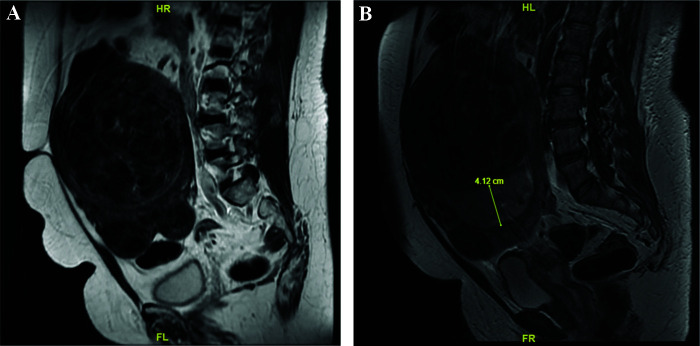

Case: A 57-year-old woman presented with a single uterine mass and intermittent bleeding over the past 4-5 years. Office endometrial biopsies, conducted twice by other providers, reported either normal endometrium or inconclusive results; therefore, she was diagnosed and managed as having uterine fibroids for the past 3 years. Given the high suspicion of uterine malignancy, we counseled the patient with a plan for an abdominal hysterectomy and bilateral salpingo-oophorectomy. Meanwhile, we performed another endometrial biopsy under sedation to obtain an adequate and accurate specimen. This biopsy revealed high-grade malignancy, leading to the diagnosis of uterine embryonal rhabdomyosarcoma following the hysterectomy. She is currently undergoing chemotherapy with docetaxel and gemcitabine.